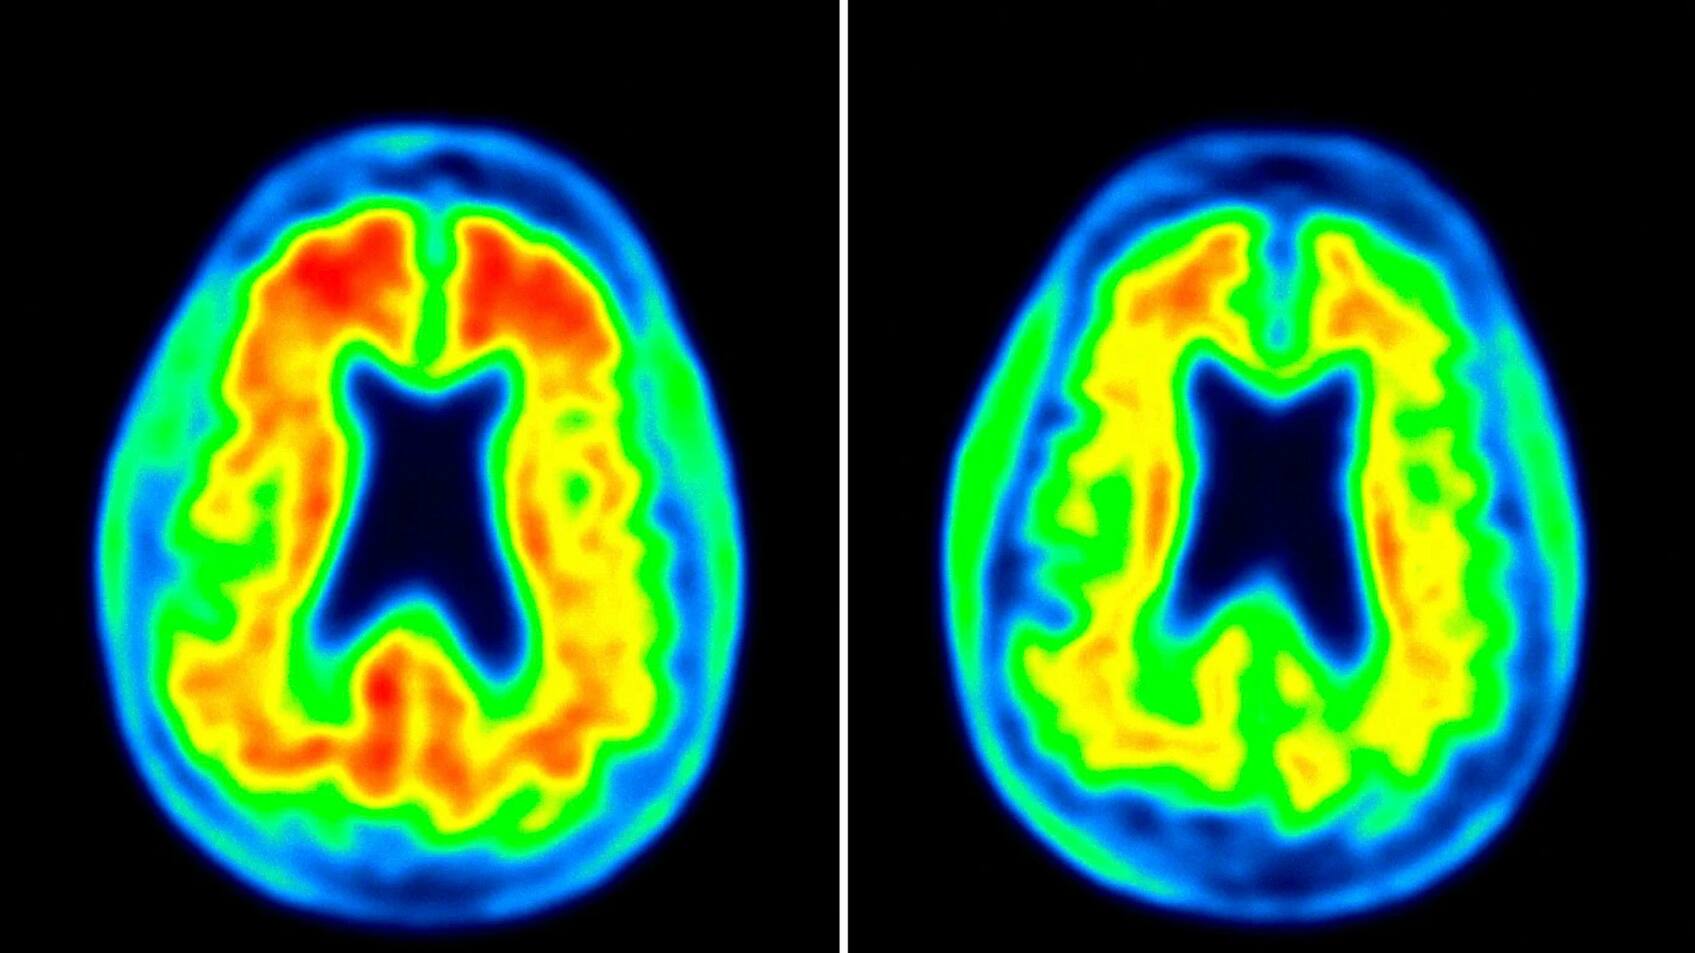

Aducanumab ist ein Heilmittel des Biotech-Konzerns Biogen, das viel Hoffnung weckt: Erstmals könnte eine Arznei nicht nur die Symptome der Alzheimer-Erkrankung mildern, sondern sogar den Krankheitsverlauf zu beeinflussen, so die ersten Anzeichen.

Der Wirkstoffkandidat Aducanumab hat eine beispiellose Geschichte hinter sich. Im März 2019 wurden die klinischen Studien gestoppt, weil es unwahrscheinlich schien, dass sich das Medikament als wirksam erweisen würde. Im Oktober kam es zu einer ersten Kehrtwende, als eine erneute Analyse der Daten den Schluss zuliess, dass sich das Medikament womöglich doch als wirksam herausstellen könnte. Die FDA und das Unternehmen einigten sich in der Folge auf einen Modus, wie die Daten zu lesen seien.